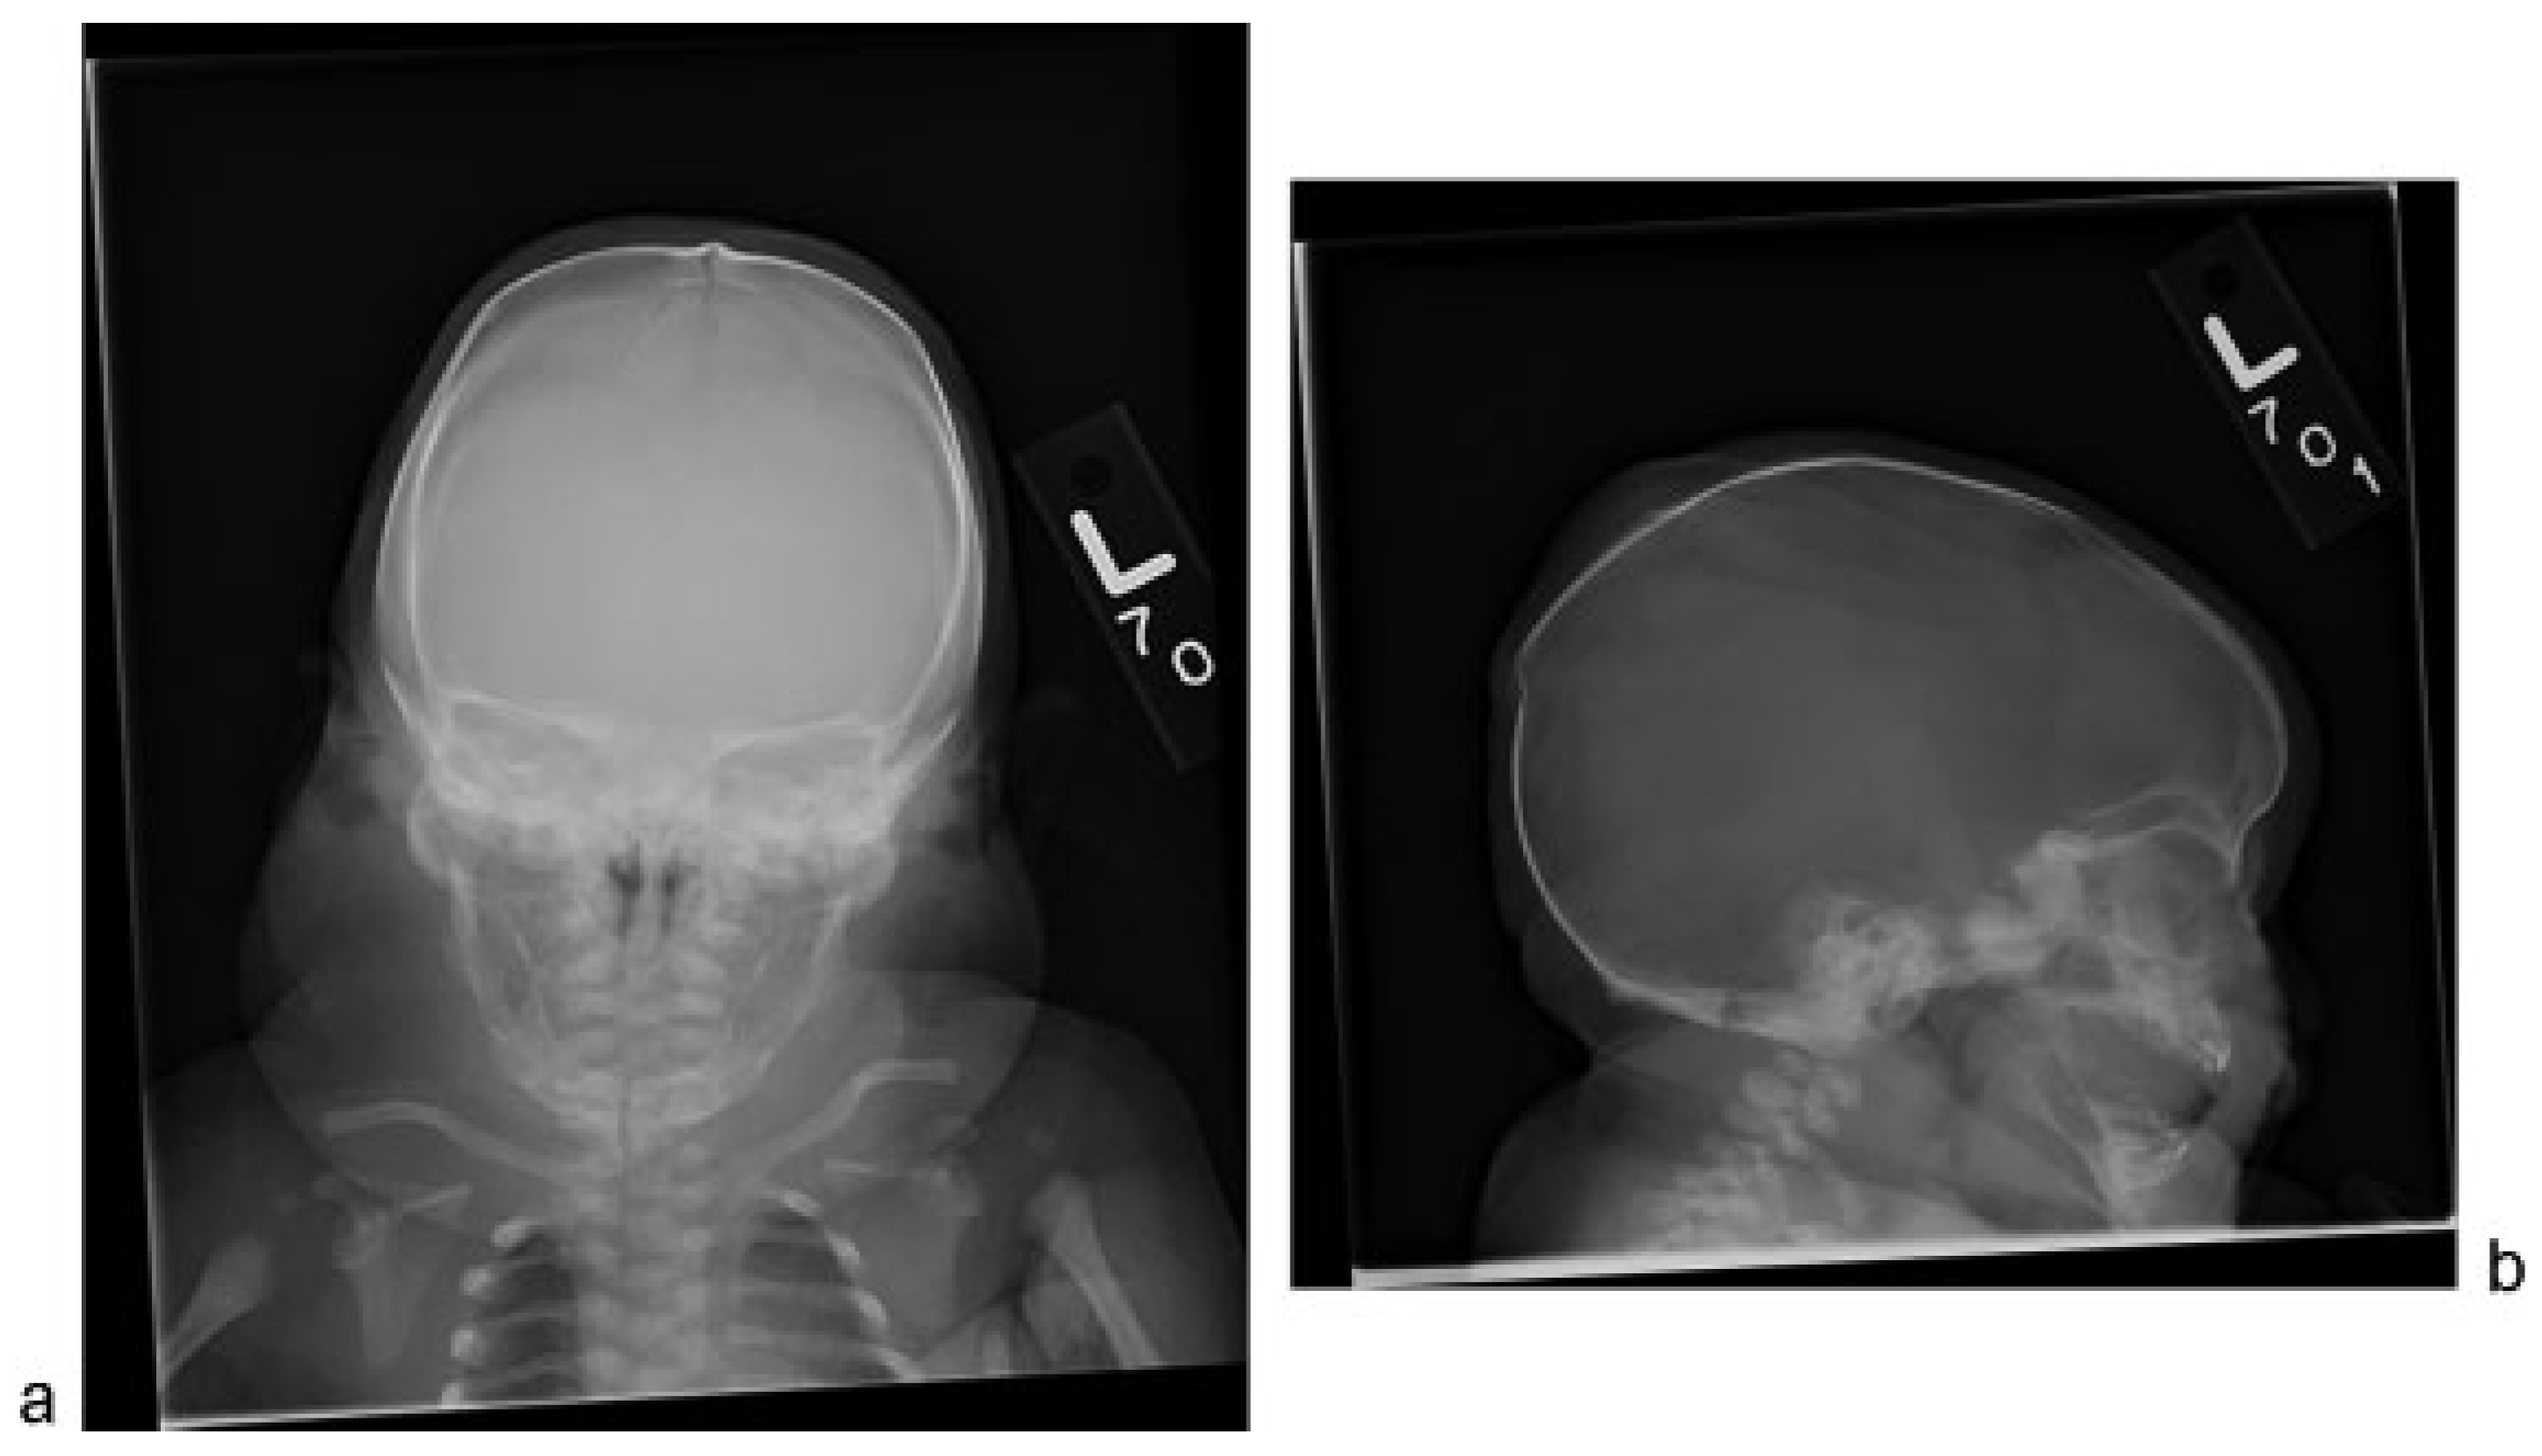

Skeletal survey confirmed sagittal craniosynostosis and a posterior parietal buckle fracture (Figure 1). Shortening and mild angular deformities of the bilateral ribs were noted. Upper extremities showed bilateral valgus deformities of the humeri, varus deformities of the proximal ulnas, radial head dislocations, and postaxial polydactyly exhibiting fusion at the base of the fifth and sixth metacarpals (Figure 2). Lower extremities showed bilateral mild varus deformities of the femurs, meso-melic shortening, relative overgrowth of the fibulas, and mild brachydactyly (Figure 3). An echocardiogram confirmed a moderately dilated and hypertrophied right ventricle with normal systolic function and revealed a small patent ductus arteriosus and a small secundum atrial septal defect.

Figure 1. (a) Frontal view of skull demonstrating sagittal suture ridging, significant soft tissue swelling about the neck and short, and angular ribs. (b) Lateral view of the skull shows dolichocephalic head shape and a posterior parietal buckle fracture.